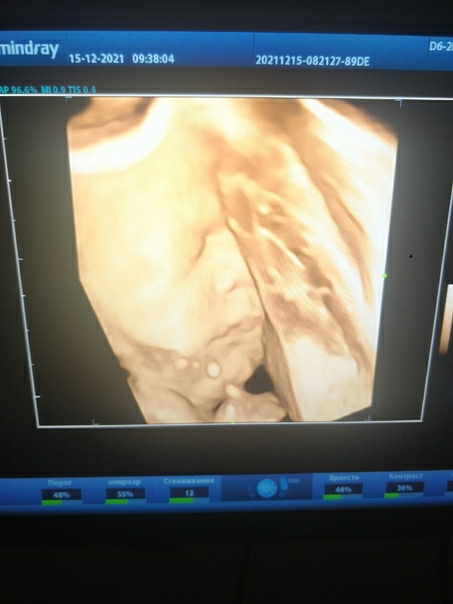

15.12.21 были на третьем скрининге. Всё хорошо, окончательно подтвердили, что будет сын (тот продемонстрировал все свои достоинства и отвернулся от датчика). Уткнулся лицом мне в бедро и всё, как хотите 😅 Если верить аппарату УЗИ, то весит уже кило девятьсот, врач прогнозирует, что к родам будет в пределах 3400-3800 🙈

Теперь знаю о причинах жестокой изжоги: сына любит упираться пятками под самый желчный 👌